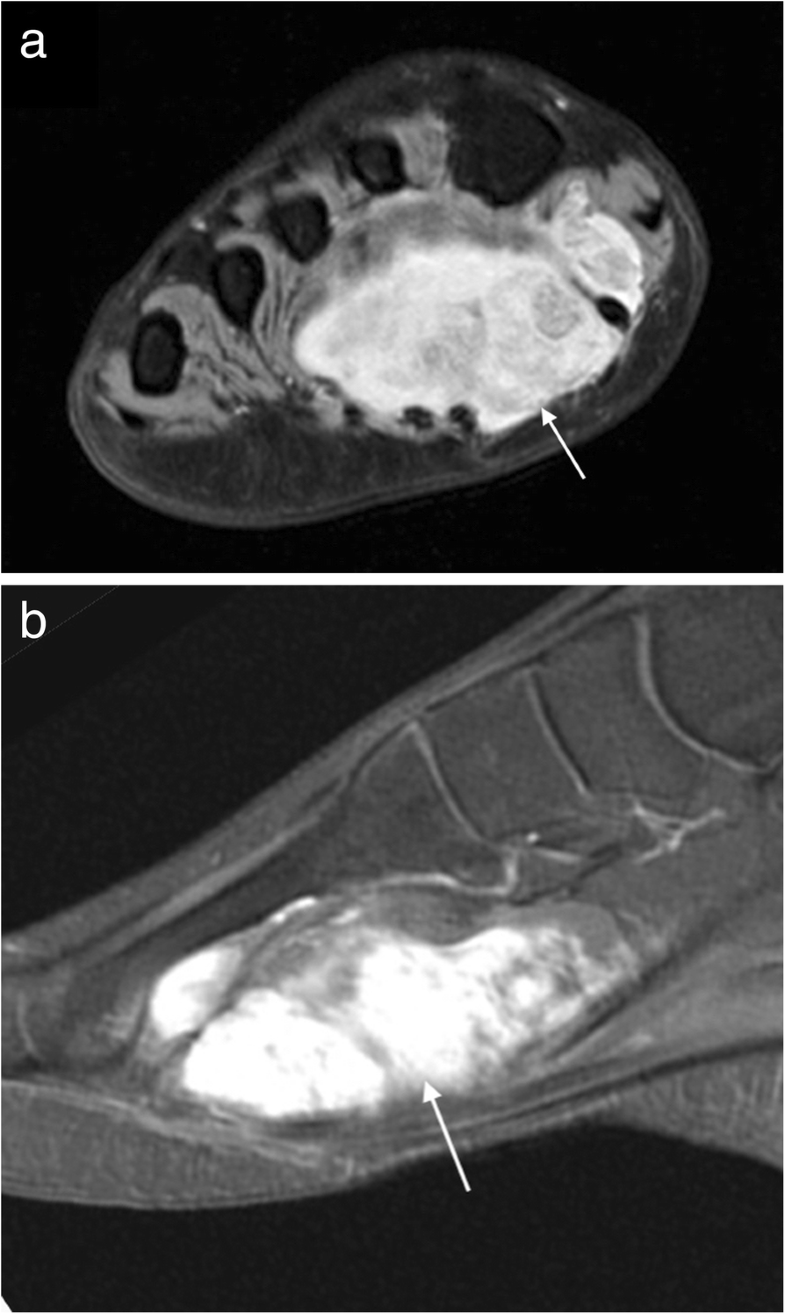

MRI imaging of soft tissue tumours of the foot and ankle Insights Plantar Foot Masses Radiology this review considers imaging features of palpable lesions around the foot that are generally benign. a plantar fibroma is a nodular mass composed of spindle cells and variable amounts of collagen that arises in the. Plantar Foot Masses Radiology.